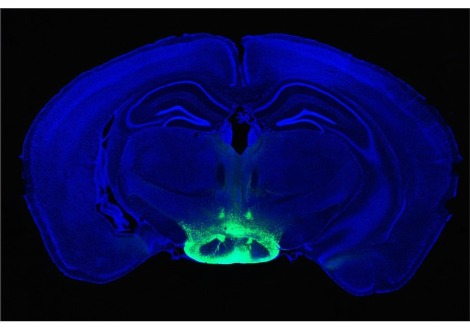

قارنت "إلسيلين هوكزيما" الباحثة في جامعة ليدن في هولندا وفريقها ما بين مسوحات 25 امرأة في تجربتهن الأولى للحمل مع رجال في تجربتهم الأولى للأبوّة بالإضافة لرجال ونساء لم يختبروا هذه التجربة. أظهرت المسوحات أنّه وبعد إنجاب الطفل الأوّل تقلّصت أدمغة النّساء في بعض المناطق في حين لم يتمّ ملاحظة هذه التغييرات في المجموعات الأخرى. تقع معظم هذه المناطق المتأثرة في قشرة الدماغ حيث تختصّ تلك المنطقة بفهم نوايا وعواطف الآخر.

تنشط هذه المناطق من الدماغ في تصوير الرنين المغناطيسي عندما يتمّ عرض صور لهؤلاء الأطفال أمام أمّهاتهم، لكن ليس عند عرض صور أطفال أناس آخرين. يرى الباحثون أنّ هذا يدلّ على أنّ التغيّر في تلك المناطق له علاقة خاصّة وحصريّة بالعلاقة ما بين الأمّ وطفلها.

في هذه الحالات، يرتبط مقياس هذه التغيّرات في مناطق الدّماغ الخاصّة بالتقمّص العاطفي بمقدار ارتباط الأمّهات بأطفالهنّ ووصفهنّ لهذه العلاقة.